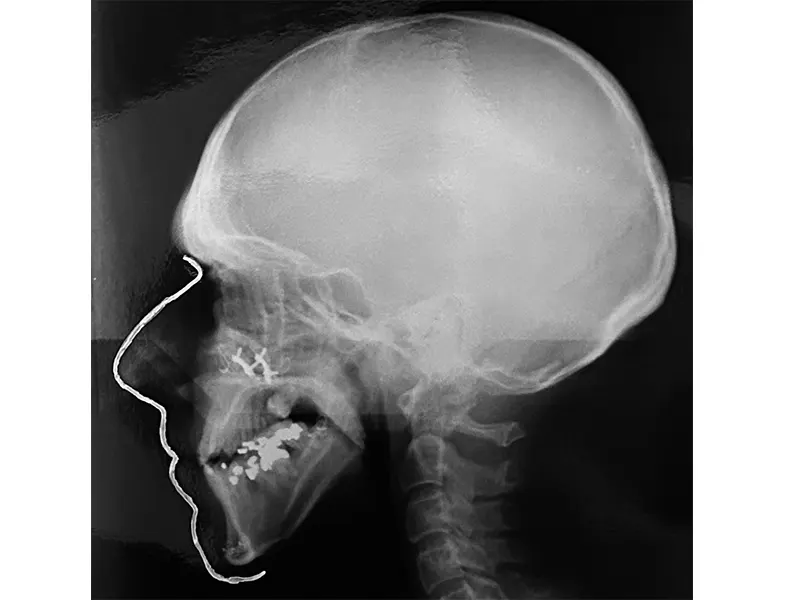

Λοιπές Αντιπροσωπευτικές Φωτογραφίες Κλινικών Περιστατικών

Στη δεύτερη υποενότητα, περιλαμβάνονται αντιπροσωπευτικές φωτογραφίες από λοιπές κλινικές περιπτώσεις. Οι εικόνες αυτές αποσκοπούν στην παρουσίαση διαφορετικών τύπων περιστατικών, επιτρέποντας την καλύτερη κατανόηση των προκλήσεων και των θεραπευτικών επιλογών. Μέσα από την ανάλυση αυτών των περιπτώσεων, επιδιώκεται η ανάδειξη της προσαρμοστικότητας των θεραπευτικών μεθόδων στις ιδιαίτερες ανάγκες κάθε ασθενούς.